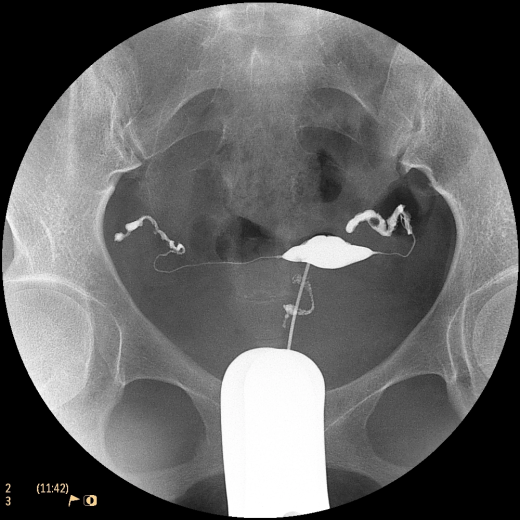

Система Philips BV Endura, рассчитанная на выполнение рутинных задач, расширяет возможности процедур на сосудах. Компактный размер 9-дюймового усилителя изображения обеспечивает маневренность для ортопедии и травматологии, а 12-дюймовый обеспечивает превосходный охват для выполнения сосудистых процедур, урологии и общей хирургии. Кроме того, мы увеличили угол поворота C-дуги до 135°, чтобы дать возможность получения проекций, необходимых для большинства процедур на сосудах.

Полностью цифровая цепь формирования изображений с матрицей 1024х1024 использует передовые средства шумоподавления и двумерного подчеркивания контуров для создания изображений с высоким качеством.

Уникальная программа BodySmart отслеживает и точно определяет поле обзора в соответствии с анатомическими структурами, вне зависимости от их положения по отношению к усилителю изображений (УИ). Это автоматически обеспечивает отличную контрастность изображений, даже если исследуемый объект смещен относительно центра УИ.